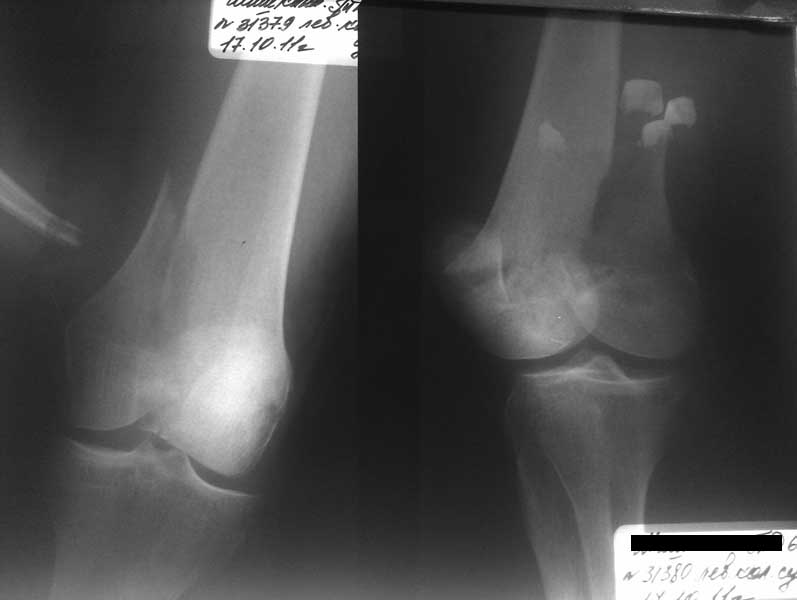

Внутрисуставной чрезмыщелковый перелом бедра

уважаемые коллеги. Подскажите метод лечения пациентки. Больная 62 г. Находилась на лечении

в терапии, где упала 17.10.11. Переведена в травм. отделение. Наложено вытяжение. Что

делать дальше?